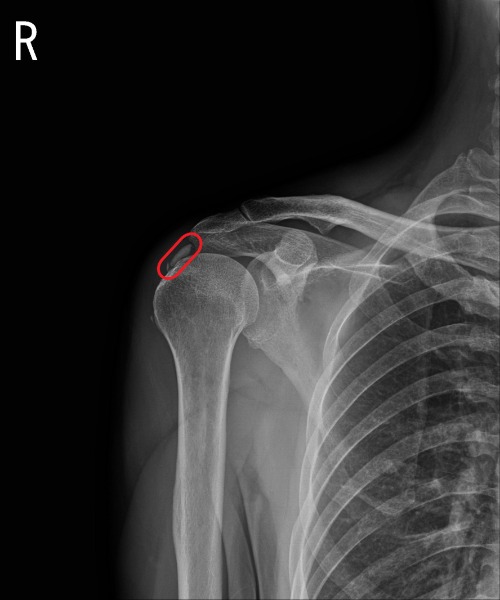

석회성건염은 힘줄에 칼슘 퇴적물이 쌓이며 극심한 통증을 유발하는 질환이다. 어느 관절 부위에나 생길 수 있는데, 보통 어깨관절에 많이 생긴다. 발병원인은 아직 밝혀지지 않고 있다. 어깨에 생기는 석회성건염은 회전근개 힘줄 속에 석회가 침착되며 염증반응을 일으켜 참을 수 없는 극심한 통증을 유발한다.

석회쇄석 시술은 초음파로 석회의 위치를 확인하면서 미세한 주삿바늘로 석회를 잘게 부숴 체내에 흡수되도록 하는 방법이다. 별도의 입원 치료 없이 외래 진료실에서 국소 마취 하에 이뤄진다. 힘줄 내에서 통증을 유발하던 석회는 기본적으로 칼슘성분이기 때문에 힘줄 밖으로 흘러나온 석회 조각들은 자연스럽게 우리 몸으로 흡수된다.

한림대학교 동탄성심병원 정형외과 정증열 교수는 “석회성건염은 환자들이 응급실을 찾을 정도로 통증의 정도가 심하며 증상이 없다가 갑자기 발생한다”며 “석회성건염이 생기면 무조건 수술적 치료를 받아야 한다고 잘못 알고 있는 경우가 많지만, 석회의 크기와 상태에 따른 비수술적 요법인 초음파하 석회쇄석술로도 치료가 가능하므로 정확한 진단이 중요하다”고 설명했다.